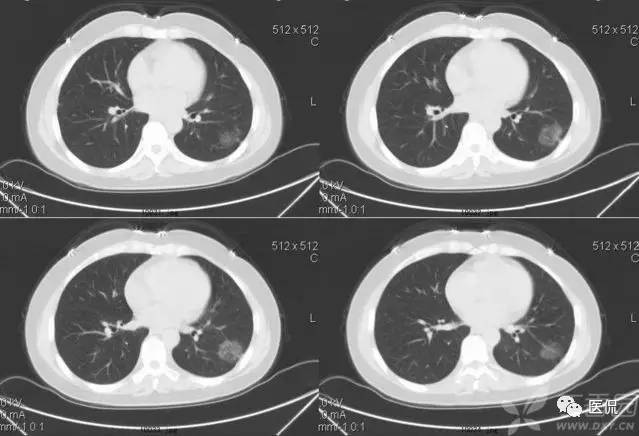

磨玻璃密度(GGO)

胸部影像上表现为肺密度的轻度增加,透过这种磨玻璃影像可以看到肺纹理的影像。该征象包括下属几种情形:1)弥漫型 如严重的急性肺移植排斥反应、早期成人呼吸窘迫综合症、肺水肿、过敏性肺炎、肺出血、各种原因的感染如非典型性肺炎等;2)斑片型 如各种类型的肺炎、肺泡蛋白沉积征、类脂质肺炎、卡氏肺囊虫病以及成人呼吸窘迫综合症等;3)局灶型 肿瘤如肺炎型肺泡癌、肺外伤、肺梗死等,这种类型常常和上述两种的病因相重叠;4)晕型 常见于早期浸袭性肺曲霉菌病,也可见于肺穿刺之后;5)支气管血管型和小叶中心型 如嗜酸性肺炎、结节病、外源性过敏性肺炎、呼吸系支气管炎等,其间前二者多见于支气管血管型,后二者多见于小叶中心型。

磨玻璃征要根据病史探求病因,如患者有出血倾向而查不出其他原因时要考虑肺出血;患者有过敏体质,又有花粉吸入或有其他过敏原接触史要考虑外源性过敏性肺炎;有多系统病变的患者要考虑结缔组织性肺炎等等。

磨玻璃影的分布对于鉴别诊断也有帮助:1)呈小叶中心分布时,一般多是早期病变,常为支气管播散,可能是过敏性肺炎或脱屑性间质性肺炎所致;2)呈全小叶分布时,病变边缘清楚;呈部分小叶受累时,病变边缘模糊。前者可见于肺泡蛋白沉积征、药物中毒性肺炎、类脂质肺炎、肺结节病、卡氏肺囊虫病、肺炎吸收期间以及肺出血等;3)呈小叶周围性分布时,多为早期特发性肺纤维化的表现。

1)肺腺癌:

2)含铁血黄素沉着症:

3)特发性肺间质纤维化: